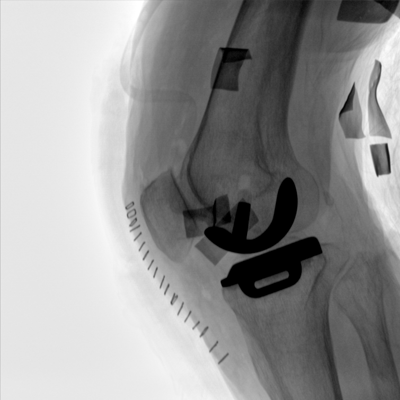

臨床適用科室:骨科、普通外科、矯形外科、創(chuàng)傷外科、泌尿外科、脊柱外科、疼痛外科、消化科、婦科等科室。

大尺寸動(dòng)態(tài)平板探測(cè)器,高DQE、低噪聲、圖像清晰。采用多分辨率圖像增強(qiáng)處理技術(shù),不同部位不同圖像處理算法,滿足客戶多樣化的需求。